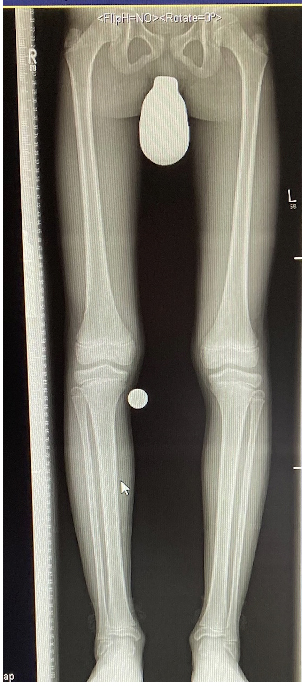

In der Regel bestehen aktive Wachstumsfugen bei Mädchen bis zum 12. und bei Jungen bis zum 14. Lebensjahr, mit Abweichungen von einem Jahr nach unten und nach oben. Präzise Informationen unter anderem darüber gibt das präoperative Röntgenbild (Abb. 2).

Abb. 2 a-c: offene Wachstumsfugen MT I Basis und Zehen (a), teilweise geöffnete Wachstumsfugen (b) und geschlossene Wachstumsfugen (c).